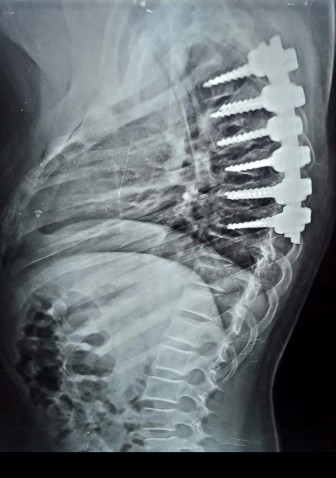

A case of kyphosis in the thoracic vertebrae of a girl at the age of ten years. The convexity was in the upper part of the thoracic vertebrae. It was caused by the impact of a solid body falling from the top of a house on the girl while she was passing under the house. This impact resulted in compression and fusion of a number of thoracic vertebrae, which led to a very, very high hunching angle, as is evident in the CT scan and MRI. Immediately after the patient was diagnosed, she was prepared for surgery to correct the deformity resulting from the kyphosis and to relieve pressure on the neural canal in the thoracic vertebrae. By the grace of God and His grace, the Almighty, the daughter was born safely to her family. The CT scan and the normal follow-up were very, very beautiful, as it was clear that the full correction of the angle of hump to the normal level.